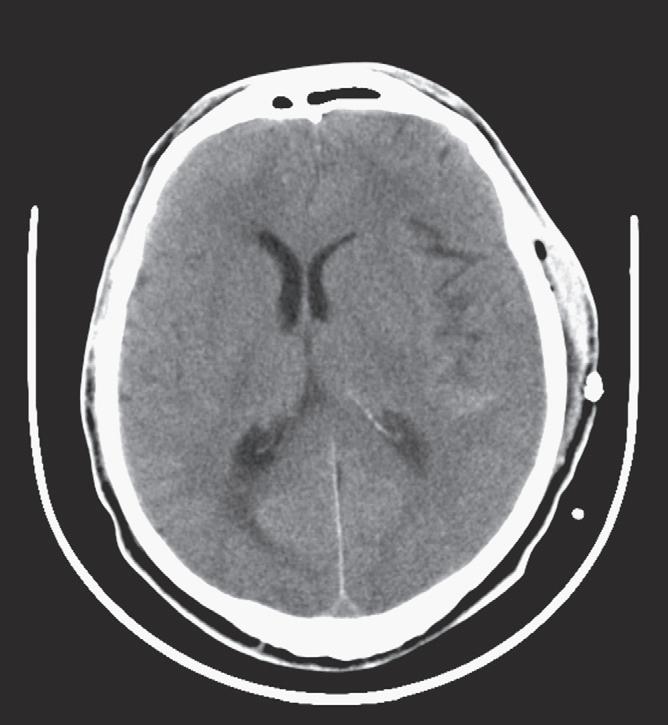

Epidural hematoma is the term generally applied to a hemorrhage that forms between the inner table of the calvarium and the outer layer of the dura because of its masslike behavior. More than 90% of epidural hematomas are associated with fractures in the temporoparietal, frontal, and parieto-occipital regions. CT is usually the most efficient method for evaluation of this type of hemorrhage.An epidural hematoma typically has a hyperdense, biconvex appearance. It may cross the midline but generally does not cross sutures (because the dura has its attachment at the sutures), although this might not hold true if a fracture disrupts the suture. Epidural hematomas usually have an arterial source, commonly a tear of the middle meningeal artery, and much less commonly (in less than 10% of cases) a tear of the middle meningeal vein, diploic vein, or venous sinus (Figs. 1-1 and 1-2). The classic clinical presentation describes a patient with a “lucid” interval, although the incidence of this finding varies from 5% to 50% in the literature. Prompt identification of an epidural hematoma is critical, because evacuation or early reevaluation may be required. Management is based on clinical status, and therefore alert and oriented patients with small hematomas may be safely observed. The timing of follow-up CT depends on the patient’s condition, but generally the first follow-up CT scan may be obtained after 6 to 8 hours and, if the patient is stable, follow-up may be extended to 24 hours or more afterward.

The appearance of ICH on a CT scan can vary depending on the age of the hemorrhage and the hemoglobin level. The attenuation of blood is typically based on the protein content, of which hemoglobin contributes a major portion. Therefore the appearance of hyperacute/acute blood is easily detected on a CT scan in patients with normal hemoglobin levels (approximately 15 g/dL) and typically appears as a hyperattenuating mass. This appearance is typical because, immediately after extravasation, clot formation occurs with a progressive increase in attenuation over 72 hours as a result of increased hemoglobin concentration and separation of low-density serum. On the other hand, in anemic patients with a hemoglobin level less than 10 g/dL, acute hemorrhage can appear isoattenuating to the brain and can make detection difficult. Subsequently, after breakdown and hemolysis, the attenuation of the clot decreases until it becomes nearly isoattenuating to cerebrospinal fluid (CSF) by approximately 2 months. In the emergency setting, one should be aware of the “swirl” sign with an unretracted clot that appears to be hypoattenuating and resembles a whirlpool; this sign may indicate active bleeding and typically occurs in a posttraumatic setting. It is important to recognize this sign, because prompt surgical evacuation may be required. The amount of mass effect on nearby tissues will depend on the size and location of the hemorrhage, as well as the amount of secondary vasogenic edema that develops.